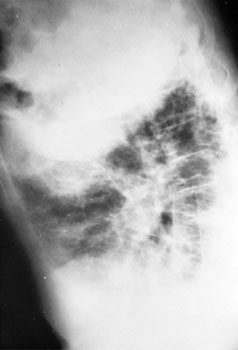

The chest x-rays presented show diffuse, severe interstitial infiltrates

without hilar adenopathy. Although sarcoidosis may produce this radiographic

picture, it is also compatible with idiopathic interstitial pneumonitis,

hypersensitivity pneumonitis, collagen vascular disease, inhalation of

inorganic dusts, and many other processes. The degree of respiratory system

dysfunction demonstrated by this patient necessitates rapid evaluation and a

definitive histologic diagnosis so that appropriate therapy can be initiated.

Angiotensin converting enzyme levels, although elevated in many patients with

sarcoidosis, are not sufficiently sensitive or specific to replace tissue

biopsy in the workup of persons with interstitial infiltrates. Although biopsy

of extrapulmonary tissue may demonstrate noncaseating granulomas in patients

with sarcoidosis, such biopsies may be negative in patients with active

disease. A pathologic diagnosis is absolutely required in patients presenting

with interstitial lung disease of uncertain etiology. Fiberoptic bronchoscopy

should be performed to rule out infection or malignancy; an accompanying

transbronchial biopsy may yield a diagnosis about 25 percent of the time.

Bronchoalveolar lavage to assess the degree of inflammation may be helpful in

monitoring disease activity, but its precise role in interstitial lung disease

has not been defined. Despite its relatively low yield, the relatively low

risk makes an attempt at transbronchial biopsy reasonable before definitely

obtaining tissue at open lung biopsy.